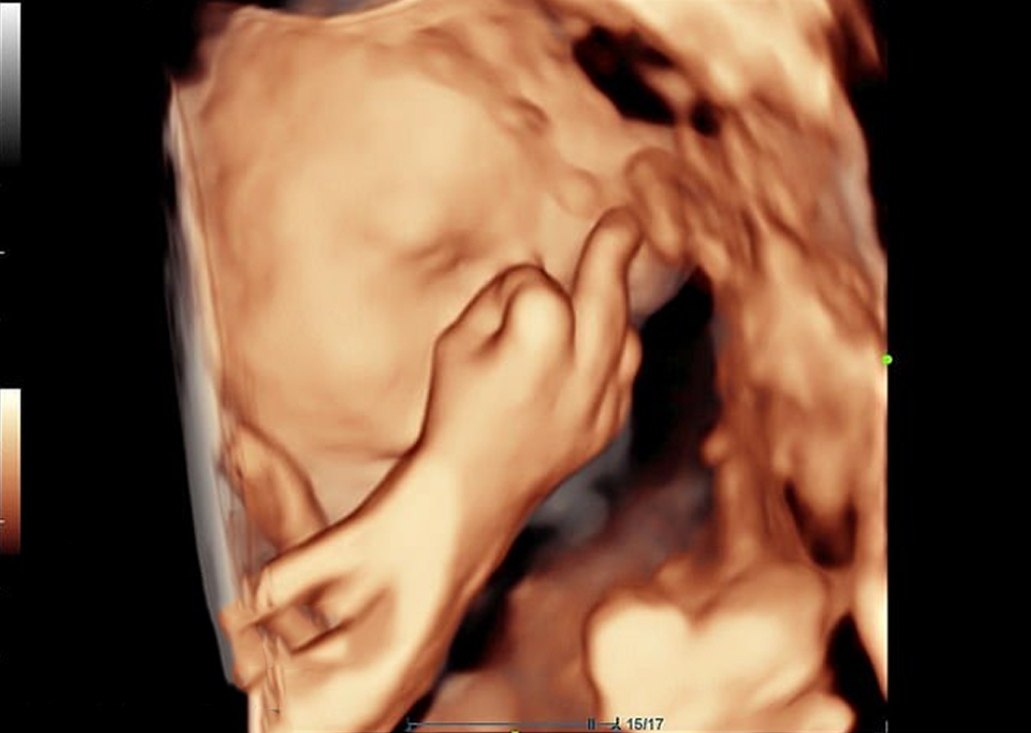

🖕 Пара британцев решила завести ребёнка в 2020 году. И он отчетливо даёт понять — время не самое подходящее. Уже на ультразвуковом сканировании видно: малыш показывает средний палец